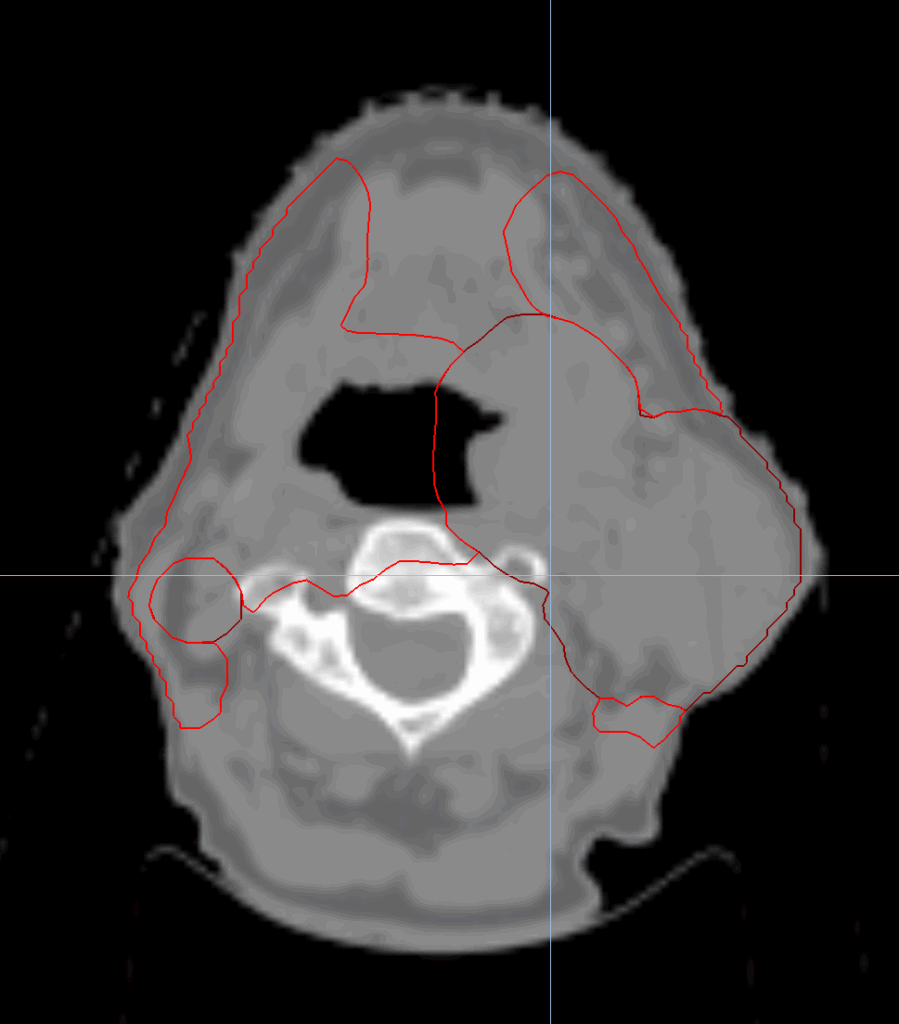

Head & Neck Oropharynx with SIB and Nodes

< View All Plan Studies RADIXACT SYSTEM Head & Neck Oropharynx with SIB and Nodes Case History AGE: 76-year-oldGENDER: Male Medical History Immidiate tolerance: Grade II dermatitis with eyelid edema, Grade I conjunctivitis resolved with Sterdex Diagnosis: Squamous cell carcinoma of the right lower eyelid Planning CT Images Treatment Plan Images ClearRT® Images Treatment Planning […]